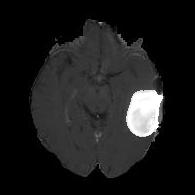

(a) (b) (c) (d)

Boundary Stream:

Fig. 2 demonstrates the output of each of the attention layers in our dedicated boundary stream. In essence, each attention layer progressively localizes the tumor and refines the boundaries. The first attention layer has learned rough estimate of the boundaries around the tumor and localized it, whereas the second and third layers have learned more fine-grained details of the edges and boundaries, refining the localization. Moreover, since our architecture leverages a dilated spatial pyramid pooling to merge the learned feature maps of the regular segmentation stream and the boundary stream, multiscale regional and boundary information have been preserved and fused properly, which has enabled our network to capture the small structural details of the tumor.